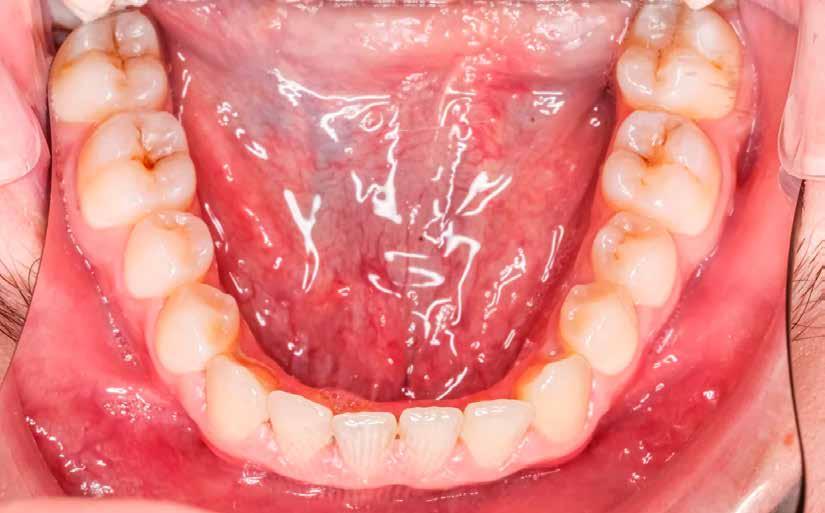

1. ábra: Nyelv helyzete az okkluzális sík felett.

2. ábra: Mallampati besorolás 4, mindegyik minimális orális térfogatot jelez.

angiotenzin II receptor antagonista) 50 mg naponta egyszer, Nexium (protonpumpa-gátló, amely csökkenti a gyomorban termelődő sav mennyiségét) (GERD) 40 mg naponta, Intuniv (multivitamin) 4 mg naponta, és aszpirin 81 mg naponta egyszer. Klinikailag a nyelv az okkluzális sík fölött helyezkedett el, hiperkeratózis (B), a nyelv légutakba való behúzódása és Mallampati 4, amely mind minimális szájüregi térfogatra utalt (1–2. ábra). Ezek indikálták az alvásfogászati készülékes kezelést. Az izomtapintás elhanyagolható volt, és az állkapocs mozgástartománya is normális volt. A maximális nyitás 45 mm volt (1–2. ábra), oldalirányú elmozdulással 12, illetve 10 mm balra és jobbra. Az állkapocs normál mozgástartománya 42–52 mm volt maximális nyitás esetén, emellett oldalirányú elmozdulás 14 mm volt [13]. Az állkapocs ízületeinek dinamikus funkcióértékelését Joint Vibration Analysis (JVA [BioResearch]) segítségével végezték, és a lágy szövetek esetében a normál határokon belülinek, valamint kétoldali porckorongok perforációjának mentesnek találták (3. ábra)